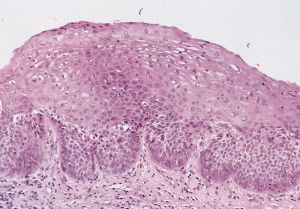

Изменения при дисплазии 1 степени обычно носят характер цитопатического действия вируса папилломы человека. В эту категорию так же относят остроконечную и плоскую кондиломы. Морфологические изменения при CIN 1 (LSIL) включают: нарушение стратификации плоского эпителия преимущественно в базальных отделах, нарушение поляризации клеток относительно базальной мембраны, единичные делящиеся клетки, незначительный дискариоз, а также признаки вирусного поражения — койлоцитарную атипию в поверхностных отделах эпителия, дискератоз, пара- и гиперкератоз эпителия.

Нарушения тканевой структуры при дисплазии многослойного плоского эпителия выражаются в утрате дифференциации различных слоёв эпителия. Верхние слои плоского эпителия бывают замещены клеточными структурами, характерными для базального слоя с нарушением процесса их созревания, дифференциации и ороговения.

Клинически дисплазия многослойного плоского эпителия проявляется в виде очаговых участков пролиферации с нарушением вертикальной дифференциации, гиперплазией клеток базального слоя, атипичным полиморфизмом клеток, нарушением нормального окрашивания и увеличением размера ядер. Верхние слои эпителия обнаруживают явления гипекератоза и дискератоза. Все описанные патологические структурные элементы в определённой степени замещают собой нормальные клеточные пласты.